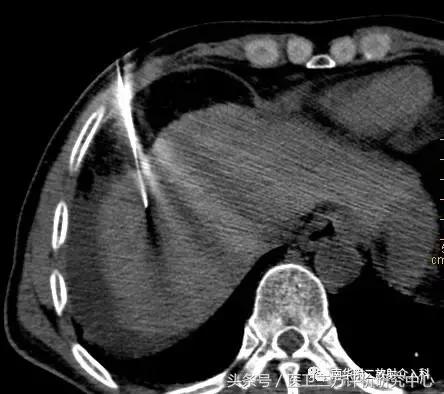

消融术前肝内病灶

CT引导精准定位